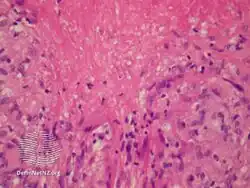

Histopathology

Lupus miliaris disseminatus faciei/pathology

Lupus miliaris disseminatus faciei/pathology-Dermatol_Sinica_2007%253B25(2)175-176-2.png.webp)